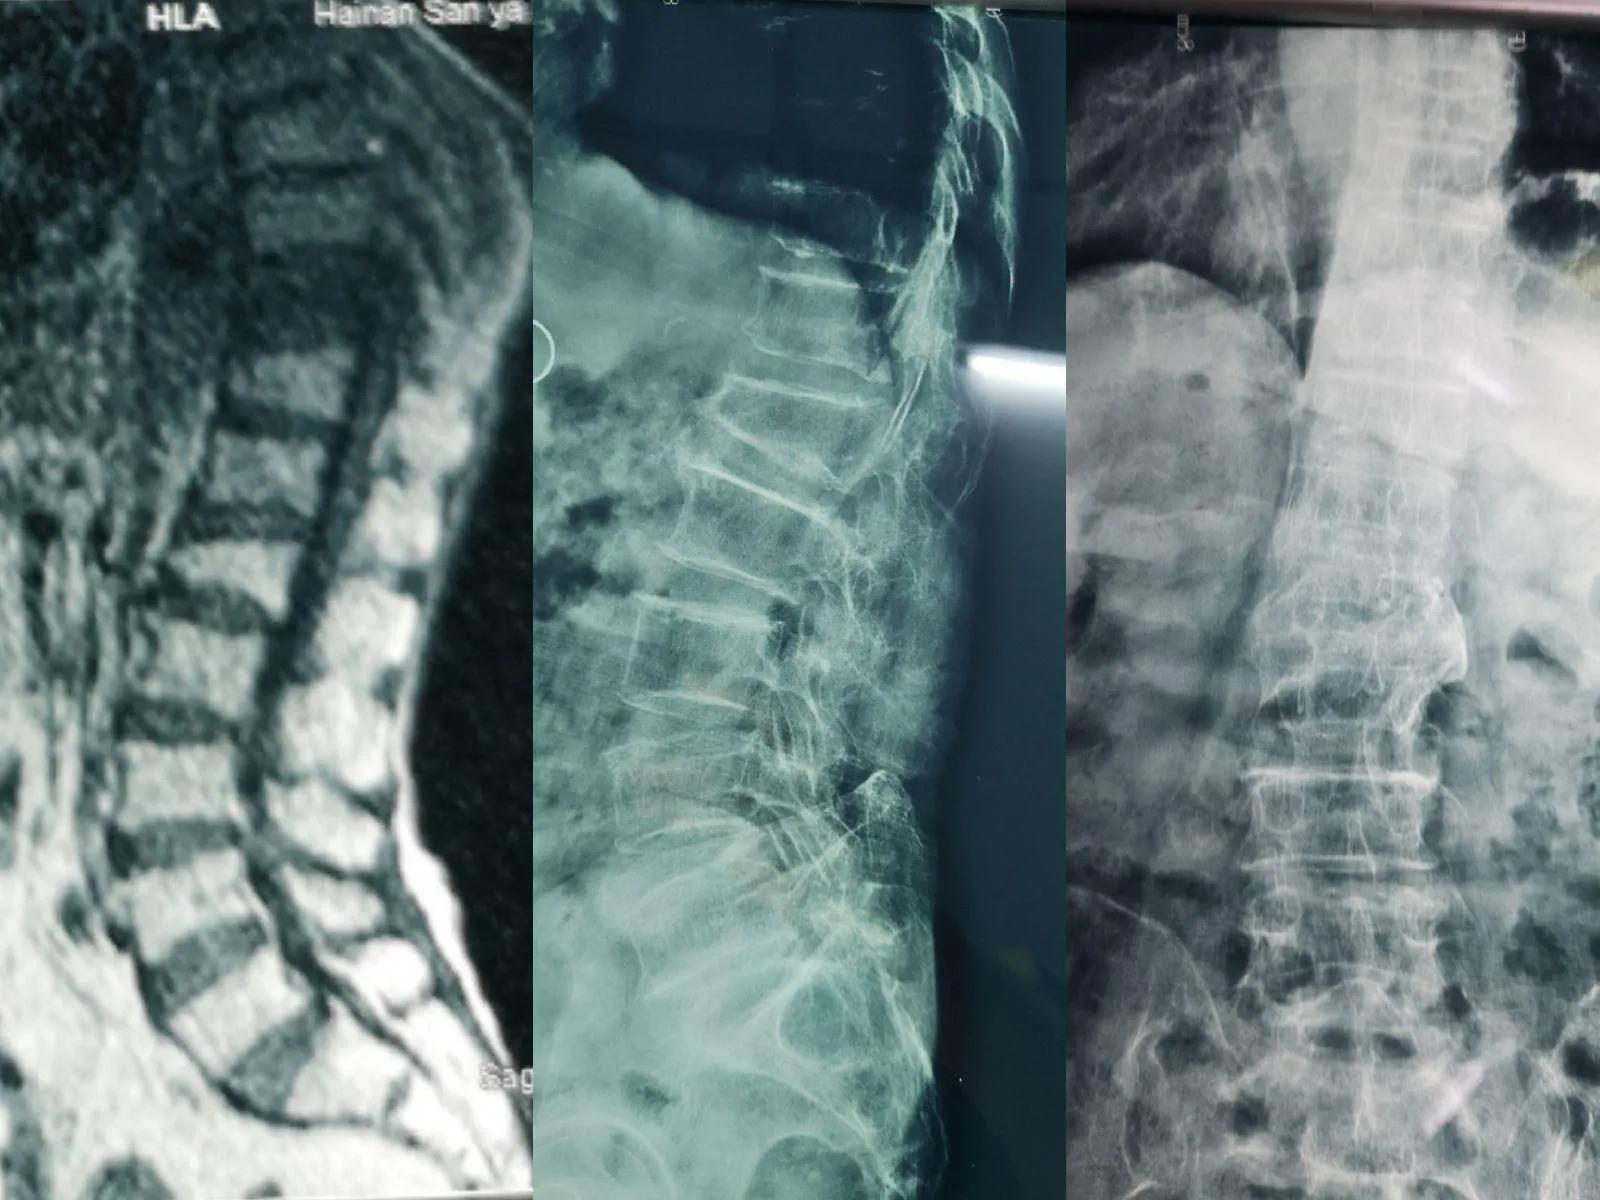

骨质疏松性椎体压缩性骨折( OVCF)常见于绝经后女性及老年男性,随着年龄增大,发生率明显增加。据统计,80岁以上女性患病率高达40%。

85岁老年女性,胸10椎体压缩性骨折